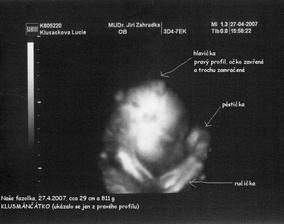

SRPŇÁTKA 2007 - fotky UTZ

album věnované mimískům, které se narodí v srpnu 2007 a jejich maminkám ze "Společného termínu SRPEN"